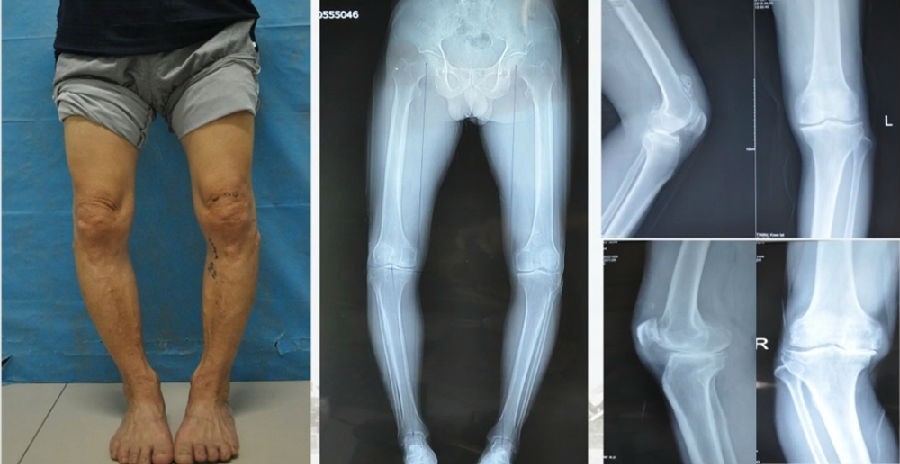

典型病例,女性,35岁,农民,左膝内翻、短缩、内旋。

术前

泰勒外固定架缓慢矫正短缩、内翻、前弓、内旋。

术中

该患者截骨后,做MAD矫正,目标MAD=0。患者术后1个月即达到设计的效果。

术后1个月

典型病例2,男性,52岁,双膝疼痛,低磷佝偻病,复合畸形。

股骨畸形即时矫正,胫骨畸形缓慢矫正。

手术前后对比

手术前后外观